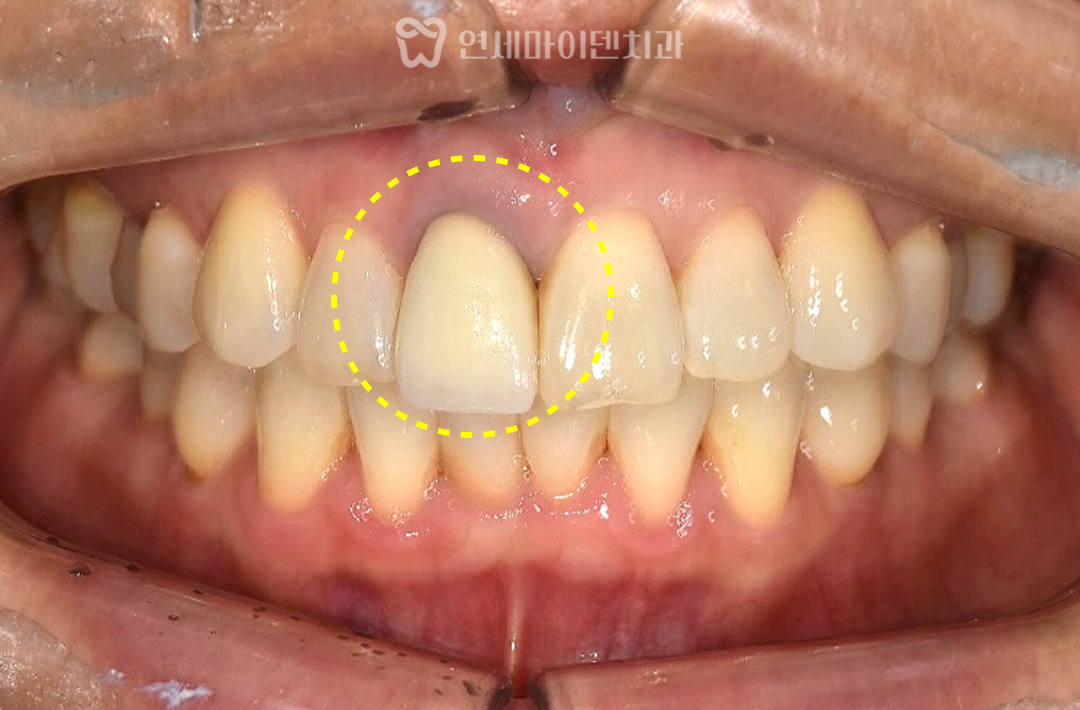

이 환자분은 과거 신경치료를 받았던

앞니의 지속적인 불편감을 호소하며 내원하셨습니다.

가만히 있어도 시큰거리고 불편한 증상이 있었고,

치근단 절제술까지 진행했지만

증상이 나아지지 않았던 상황이었습니다

4️⃣ 최종 보철물 제작

치료가 마무리된 후, 보철물을 제작하여

기존 치아와 자연스럽게 조화되는 크라운을 완성했습니다.

​치아 색과 투명도를 정밀하게 조정하여

주변 치아와 구별되지 않을 만큼 심미적으로 자연스럽게 맞췄습니다.